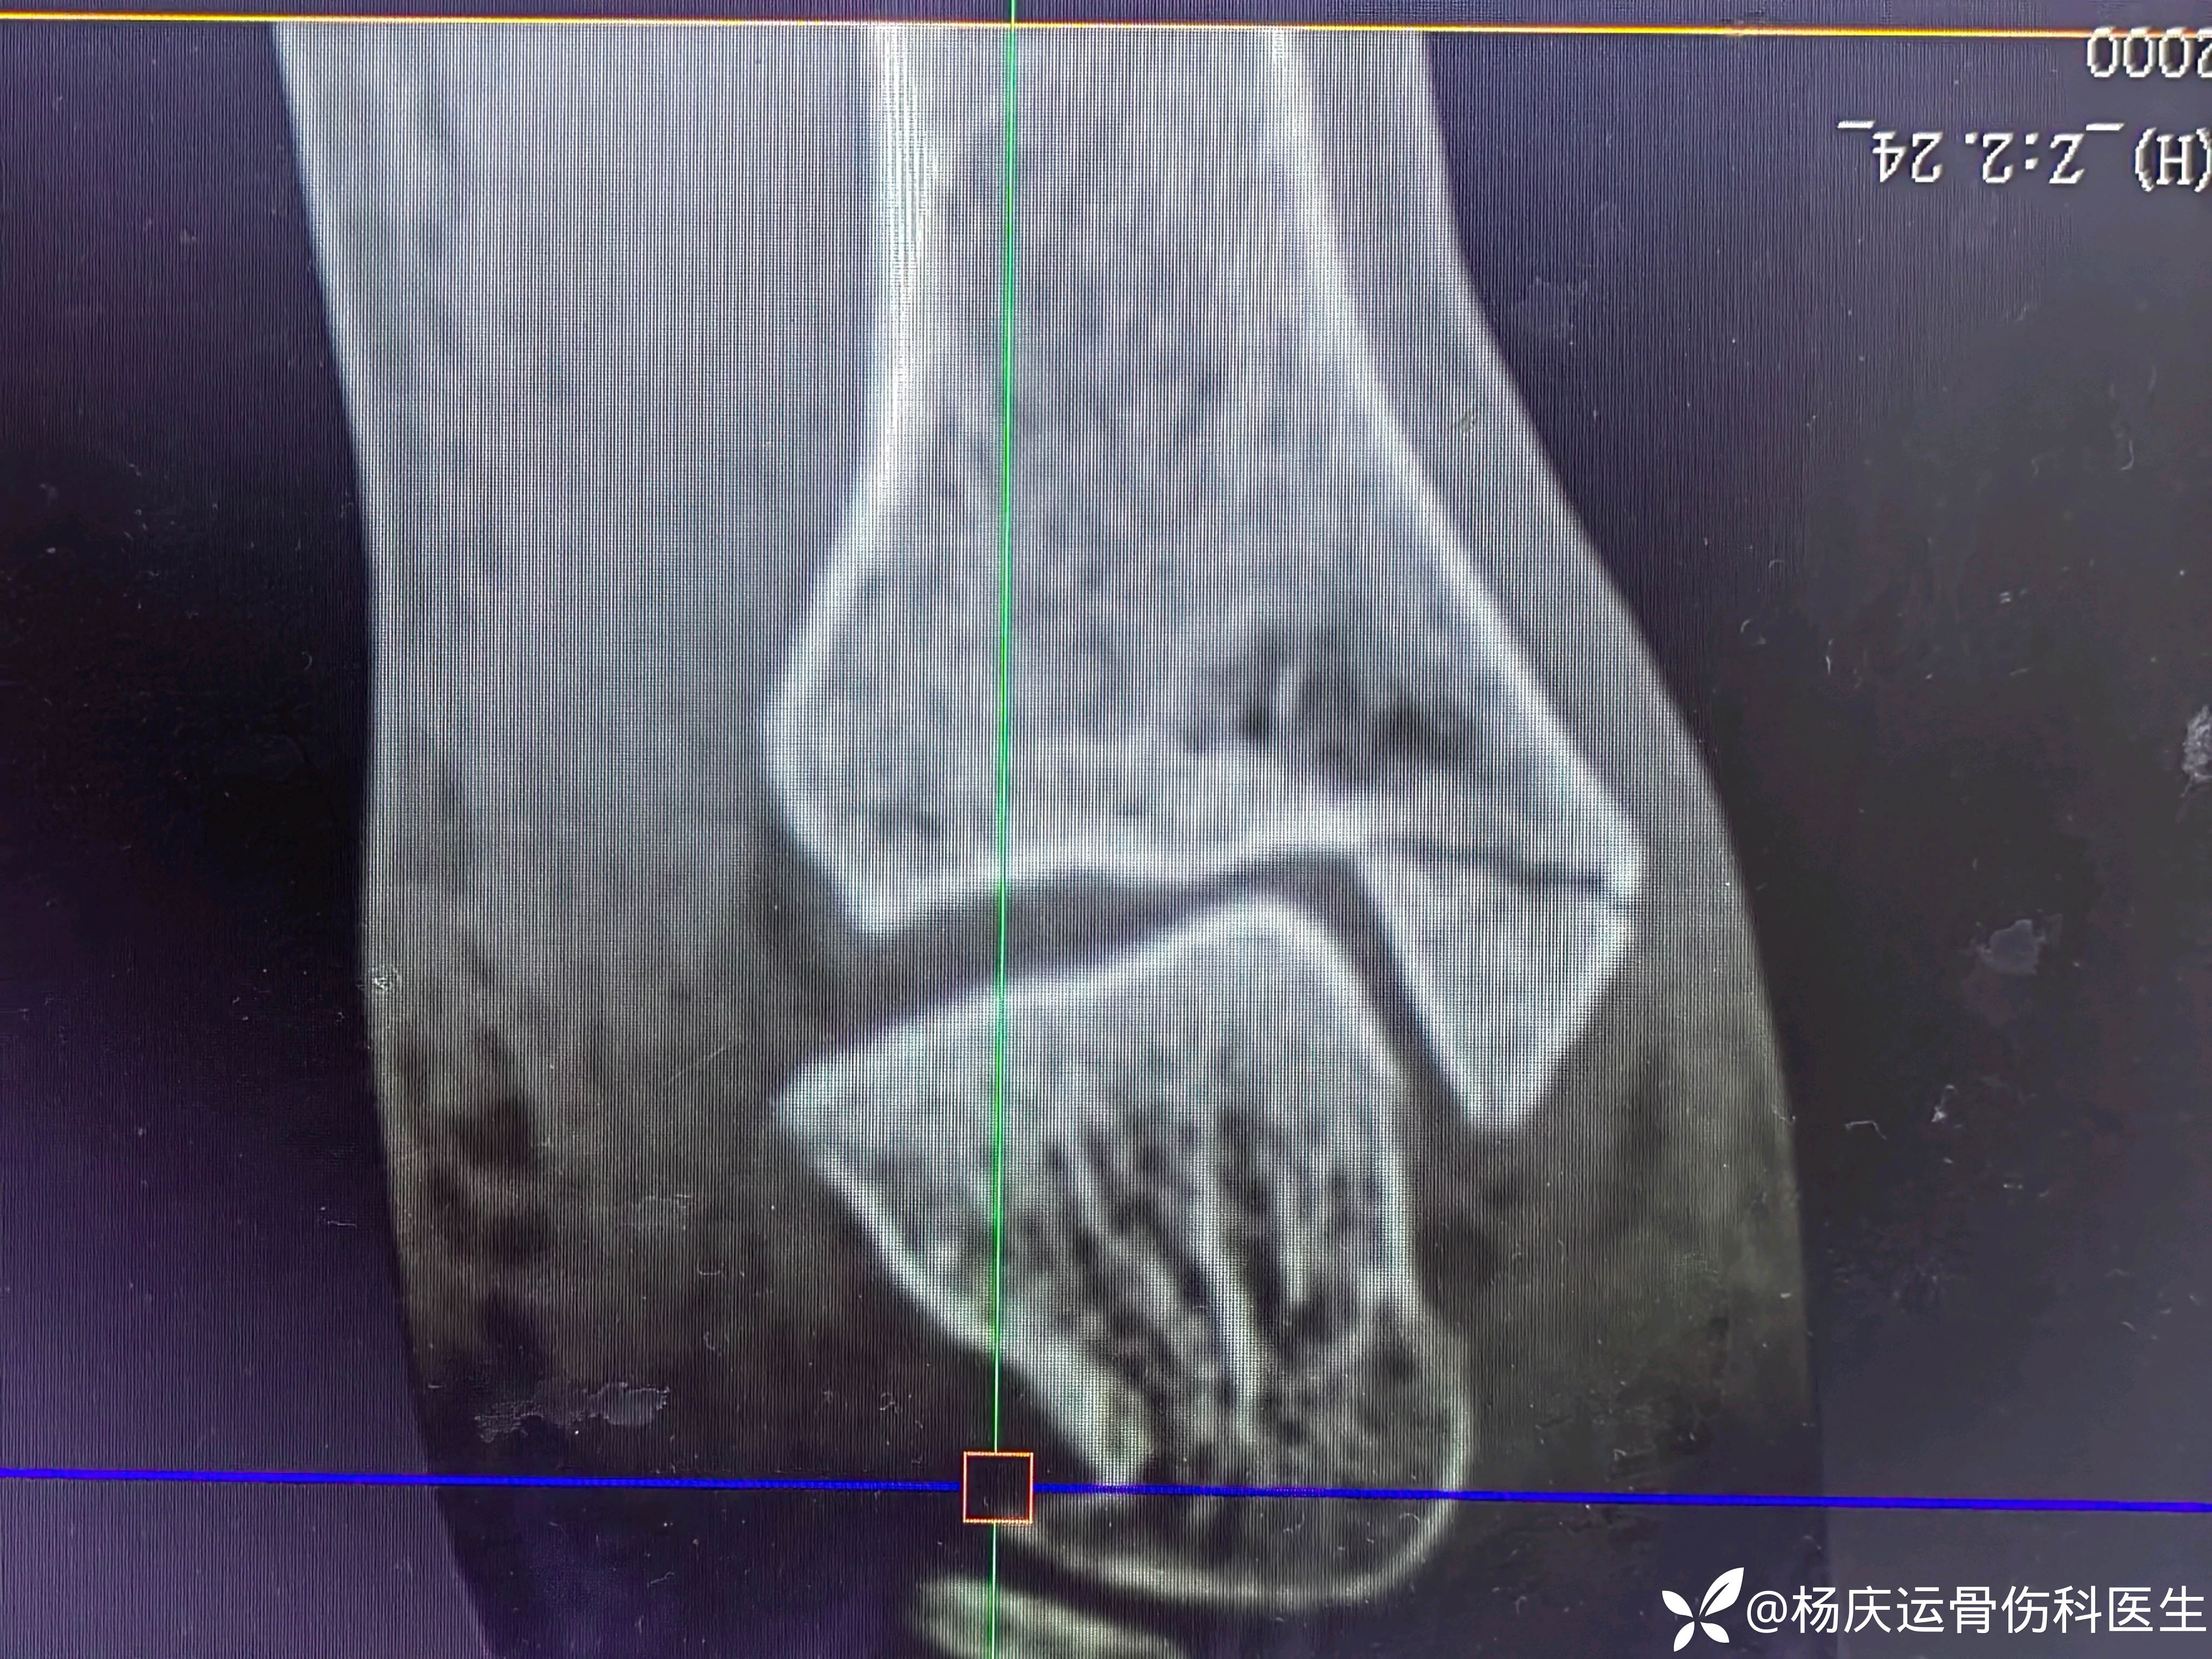

患者矫,女,66岁,左踝扭伤肿痛畸形2小时

初步诊断:左踝关节骨折(L-H分型:旋后外旋型IV)

CT